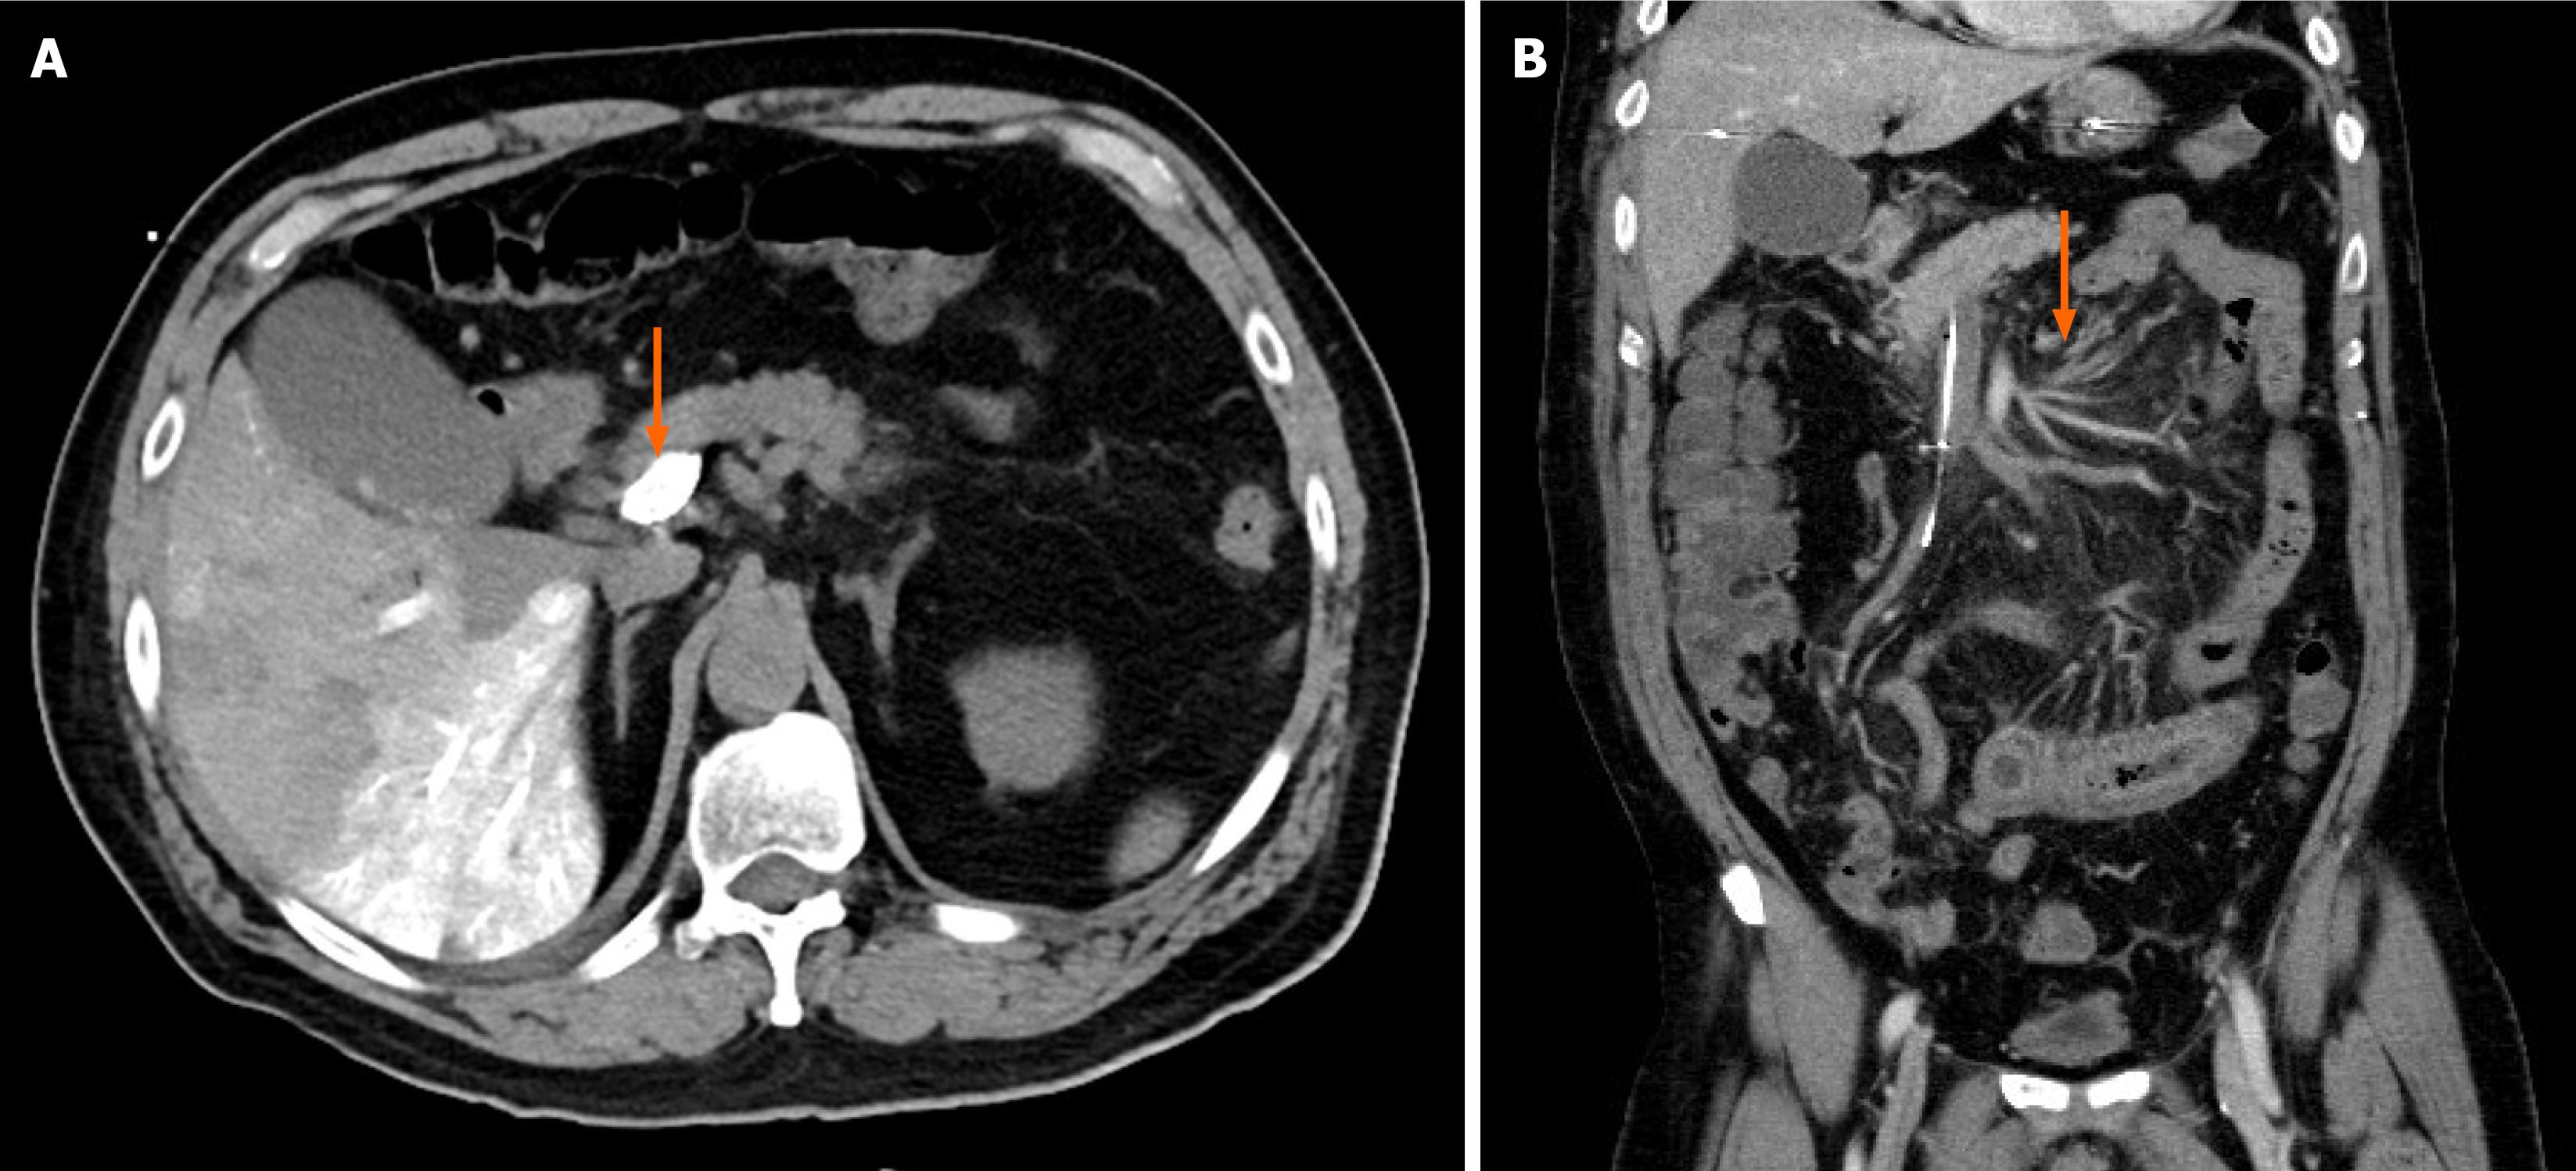

Contrast-enhanced abdominal computed tomography (CT) demonstrated a completely occlusive PVT extending into the superior mesenteric vein without evidence of cavernous transformation. Segmental small bowel wall thickening with fatty stranding, suggestive of an ischemic process, was observed (Figure 1).

The patient experienced a self-limited episode of melena, resolving after urokinase tapering. His abdominal pain also subsided. The fibrinogen concentration decreased steadily throughout the course of treatment but remained above 100 mg/dL. A follow-up portal vein venography demonstrated portal vein patency with residual filling defects in the superior mesenteric vein branches, indicating partial thrombus resolution (Figure 2). After completing 14 days of CDT, the patient tolerated a soft diet and resumed normal bowel function. He was discharged on a therapeutic regimen of clopidogrel and apixaban.